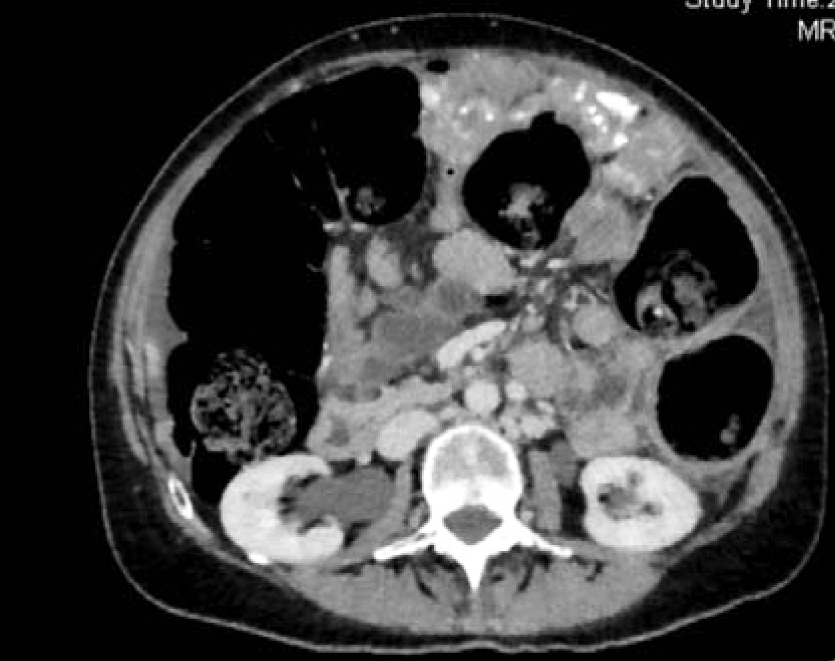

A 55-year-old female with no significant PMH and who had been postmenopausal for five years, presented with the complaint of abdominal pain, bloating, nausea and vomiting that initially occurred three months before admission. Her symptoms started with indigestion, then progressed to nausea, vomiting, bloating and abdominal pain. She presented to an outside hospital, where an obstruction series noted several air fluid levels and haziness suspicious for ascites. A CT abdomen pelvis revealed large ascites, 11x8.7 cm heterogeneous mass displacing the uterus anteriorly and a 7x5.5cm heterogeneous mass in the right adnexa and omental nodularity (Figure 1, 2, and 3). The patient was then referred to a gynecologic oncologist due to suspicion for a gynecologic malignancy and sent to our ER for ongoing abdominal pain, nausea, vomiting and bloating.

Figure 1: CT scan abdomen and pelvis. Splenic implant present.

Figure 2: CT scan abdomen and pelvis. Large ovarian mass.

Figure 3: CT scan abdomen and pelvis. 11 x 8.7cm heterogeneous mass displacing the uterus anteriorly.